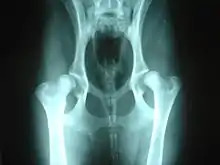

Hereditary orthopedic diseases are mainly found in purebred dogs. Hip dysplasia is a common problem that primarily affects larger breeds. Hip dysplasia is a defect in the shape of the hip joint which can, depending on the degree of hip luxation, be quite painful to the dog as it ages. Over time it often causes arthritis in the hips. Dysplasia can also occur in the elbow joint. Luxating patellas can be a problem for smaller breeds. It can cause lameness and pain in the hind legs.